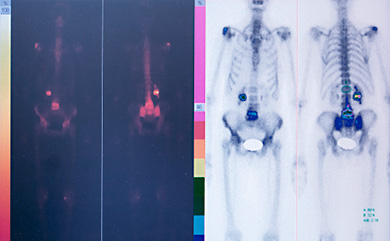

Изотопные исследования — функций костей, органов и тканей.

ПЭТ-КТ и ПЭТ-МРТ – позитронно-эмиссионная и компьютерная томографии, сканер, предоставляющий мультимодальную визуализацию, включая параметры функциональности, анатомию и молекулярные процесс. Уникальная технология Time of Flight компании «Philips» позволяет завершить проверку в течении получаса (ранее пациент проходил две проверки отдельно ПЭТ-КТ и МРТ). Эффективно при диагностике злокачественных опухолей, оценке эффективности проводимого лечения, оценке состояния миокарда, диагностика болезней – Паркинсона, Эпилепсии, Альцгеймера.

1. Более точные результаты 2. Более высокое разрешение снимков 3. Низкая доза облучения пациента (на 30% ниже в сравнении с обычной дозой облучения) 4. Эффективнее — занимает меньше времени

Ядерная медицина – общая сцинтиллография и сцинтиллографические процедуры на сердце.

Современная Гамма-камера – предназначена для визуализации и исследования кинетики радиофармпрепаратов во внутренних органах и физиологических системах организма пациента. Проводится путём сканирования всего тела пациента (скелета) и компьютерной томографии внутренних органов с целью получения трёхмерной визуализации для ранней диагностики онкологических, сердечно сосудистых заболеваний, проблем щитовидной железы, почек, печени и желчного пузыря, головного мозга, лёгких, сердца и другие. Преимуществом является её конструктивная и эксплуатационная простота.